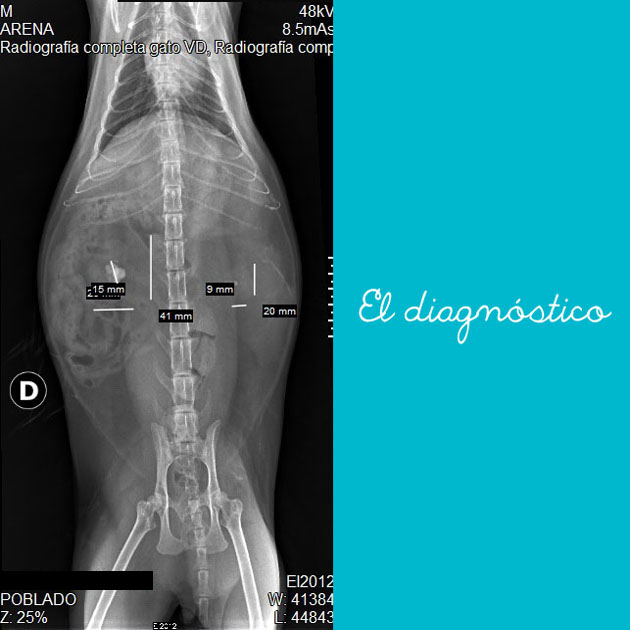

Un año después, Balín tuvo una crisis. No podía orinar, se obstruyó dos veces, fue operado y le extrajeron un cálculo de la vejiga. Después de otros exámenes como: Rx, ecografía, ionograma y citoquímico, fué diagnosticado además con cálculos en los riñones (Nefrolitiasis) de oxalato, osea los que no se disuelven. Para agravar el cuadro, la IRC había avanzado y ya Balín tenía el riñón derecho de 2 cm., probablemente atrofiado en su totalidad y con cálculos muy pequeños. El riñón izquierdo medía 4 cm. es decir, estaba inflamado porque tenía un cálculo de 15 mm aprox.